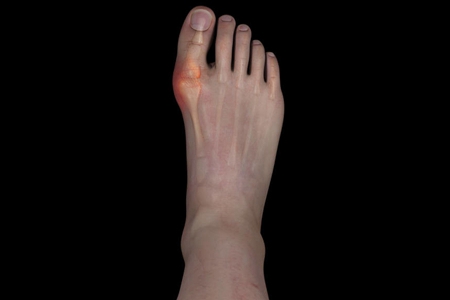

痛风石与慢性痛风关节炎期

随着间歇期的缩短,疼痛逐渐的加剧,受累关节也逐渐增多,持续的高尿酸水平导致了尿酸盐结晶析出并沉积在软骨,关节的滑膜、肌腱和多处软组织处形成痛风石。不断增多的痛风石及炎症的反复发作导致关节僵硬、活动受限乃至畸形。